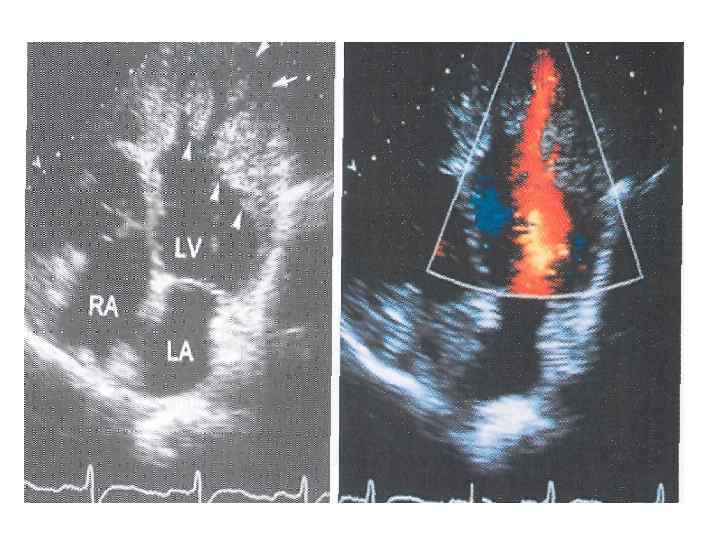

ДКМП Критерии диагноза • Фракция выброса левого желудочка менее 45% • Конечный диастолический размер левого желудочка превышает более, чем на 17% значение, откоррегированное по возрасту и поверхности тела

ДКМП Критерии диагноза • Фракция выброса левого желудочка менее 45% • Конечный диастолический размер левого желудочка превышает более, чем на 17% значение, откоррегированное по возрасту и поверхности тела

ДКМП Симптоматика • Кардиомегалия • Сердечная недостаточность (снижение переносимости физической нагрузки, прогрессирующая одышка, сердцебиение, отеки) • Нарушения ритма сердца • Тромбоэмболические осложнения • Систолические шумы на МК и ТК • Боли в груди

ДКМП Симптоматика • Кардиомегалия • Сердечная недостаточность (снижение переносимости физической нагрузки, прогрессирующая одышка, сердцебиение, отеки) • Нарушения ритма сердца • Тромбоэмболические осложнения • Систолические шумы на МК и ТК • Боли в груди

Методы диагностики ЭКГ • нормальная или с неспецифическими изменениями • атриовентрикулярные и внутрижелудочковые блокады • нарушения ритма сердца, МА у 20%

Методы диагностики ЭКГ • нормальная или с неспецифическими изменениями • атриовентрикулярные и внутрижелудочковые блокады • нарушения ритма сердца, МА у 20%